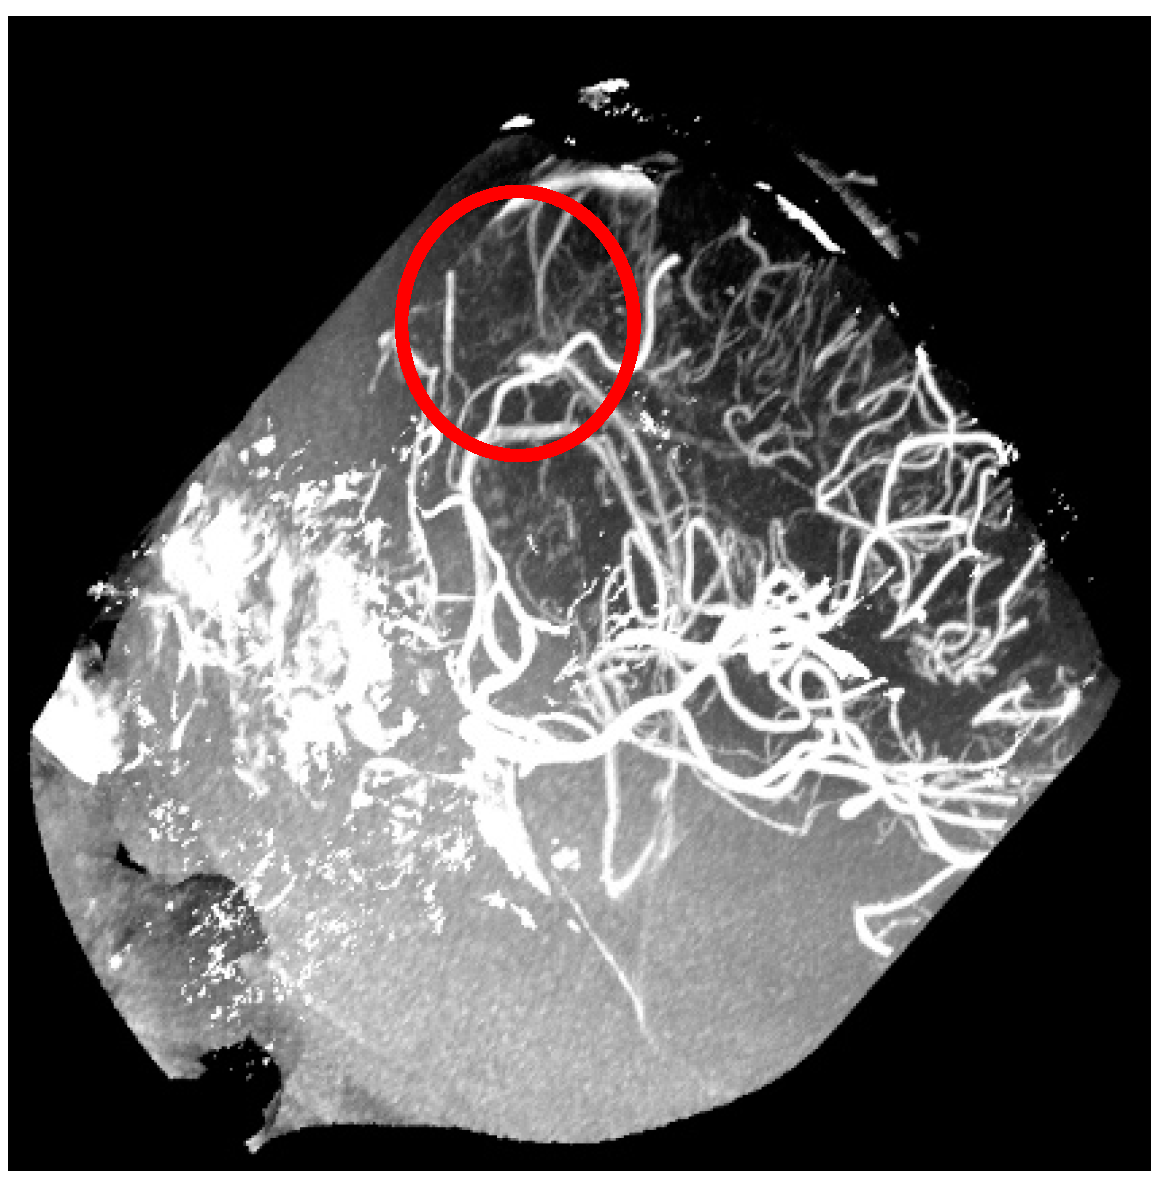

- Aziz, A.A.; Izhar, L.I.; Asirvadam, V.S.; Tang, T.B.; Ajam, A.; Omar, Z.; Muda, S. Detection of Collaterals from Cone-Beam CT Images in Stroke. Sensors 2021, 21, 8099. [Google Scholar] [CrossRef]

- Ali, N.H.; Abdullah, A.R.; Saad, N.M.; Muda, A.S. Brain cone beam computed tomography image analysis using ResNet50 for collateral circulation classification. Int. J. Electr. Comput. Eng. 2023, 13, 5843–5852. [Google Scholar] [CrossRef]